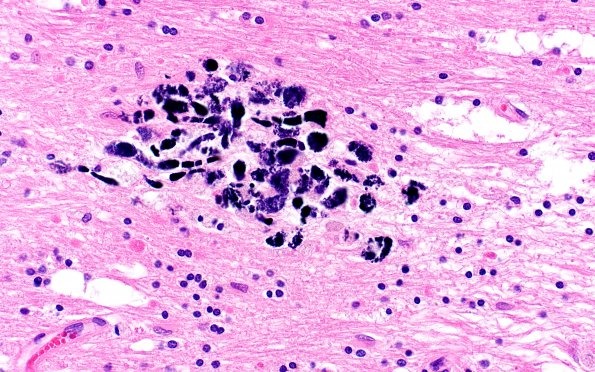

Washington University Experience | MYELIN (NON-IMMUNE MEDIATED) | Retinal Vasculopathy with Cerebral Leukoencephalopathy (RVCL, TREX1 Mutation) | 17C9 RVCL (Case 17) N13 H&E 40X 2

Calcifications involve macrophages and decorate axons and swellings. (H&E)